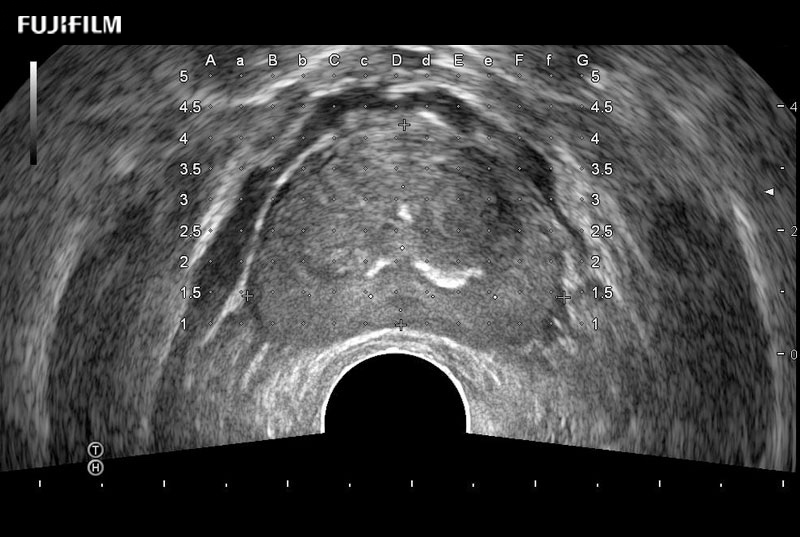

Exclusive 200° FOV end-fire prostate biopsy transducer.

Main Specifications:

Provides real-time imaging of both the sagittal and transverse planes